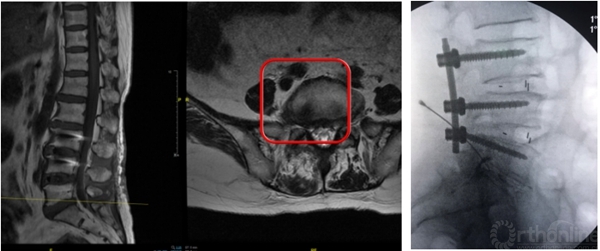

高度脱垂病例可选择椎板开窗入路,需准备磨钻动力系统

L5/S1钙化型突出(骺环离断症),椎板间减压更加充分彻底,需配备磨钻动力系统

特殊工具的准备:磨钻动力系统、可弯曲髓核钳等;